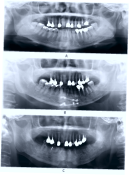

Этап 2

Ортопантомограмма + фотопротокол

Для выявления объема костной ткани в области отсутствующих зубов

Этап 3

Компьютерное 3D моделирование операции

Для подбора необходимых размеров имплантов, ориентируясь на высоту и толщину костной ткани